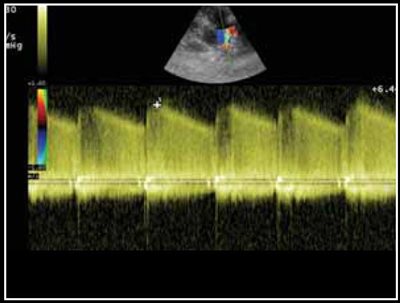

Photo 7 - Mesure de la vitesse du flux de canal en mode Doppler continu. Flux typique de canal systolo-diastolique avec une phase diastolique de plateau descendant.

Du fait du différentiel de pression entre aorte et tronc pulmonaire, le shunt est le plus souvent gauche-droit. Ce shunt est visible en mode Doppler couleur (Photo 6), et mesurable en mode continu (Photo 7).

Classiquement il s’agit d’un flux systolodiastolique typique, avec une phase de plateau descendant en diastole (Photo 7) [2,3].